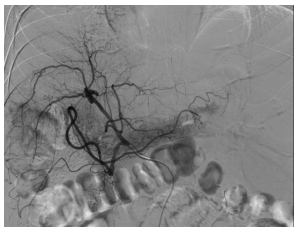

造影显示患者肝右叶肿瘤染色